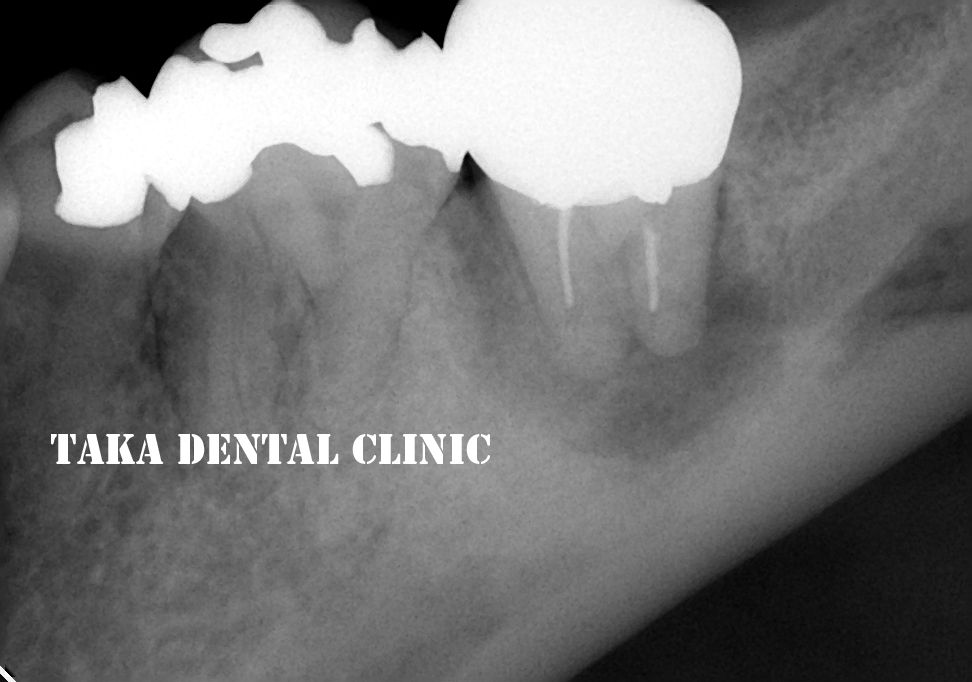

↑初診時

歯肉から膿が出て、咬むと痛む、若干歯が動いていると来院されました。確かにレントゲン写真では、大きな病気が出来ています(根の周りの黒い影)。